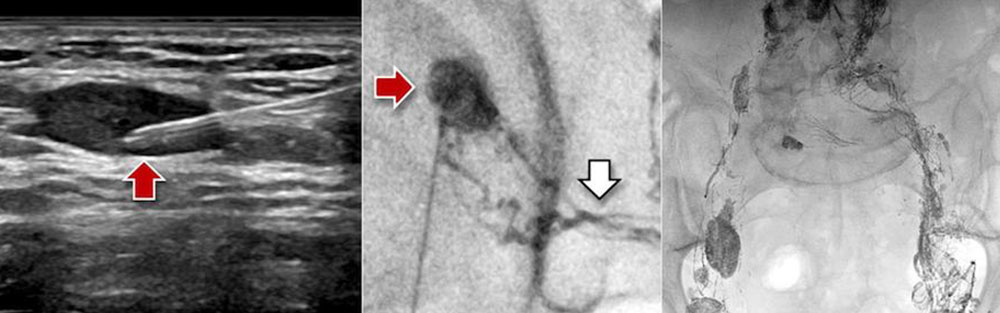

Intranodal lymphangiography (INL) is used for direct imaging of central conducting abdominal and thoracic lymphatic vessels after injection of an oily X-ray contrast medium (Lipiodol) into inguinal lymph nodes under ultrasound guidance. This new procedure has practically replaced the conventional bipedal lymphangiography, in which a lymph vessel on the back of the foot is surgically prepared and injected with dye.

Opacification of the lymph vessels after sonographic insertion of a thin needle into inguinal lymph nodes on both sides at the border between medulla and cortex of the lymph node must be performed very slowly, preferably using injection pumps, in order to avoid contrast medium leakage from the thin-walled lymph vessels. The outflow of the contrast medium through the central lymphatic ducts of the pelvis, abdomen and chest to the entrance in the left venous angle is anatomically variable. Illustration of the individual anatomy is performed by fluoroscopy.